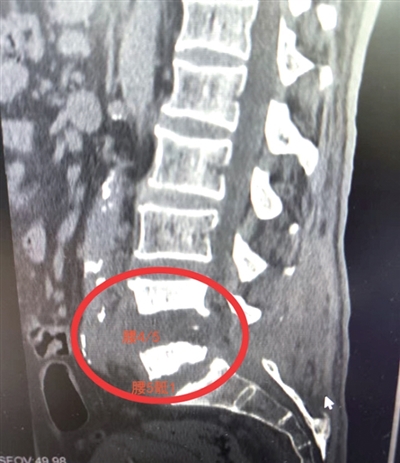

患者腰4/5、腰5骶1椎间盘几乎被细菌“吃”光 医院供图

“看了患者的片子,吓一跳,化脓性脊柱炎,腰4/5,腰5骶1的椎间盘几乎被细菌‘吃’光。虽然经历了几次清创,但感染没有彻底清除。”范主任进一步解释,“如果坏死的椎间盘没有被彻底清除,就会持续成为细菌的培养皿,始终会有细菌蜂拥而至,感染就好不了。”